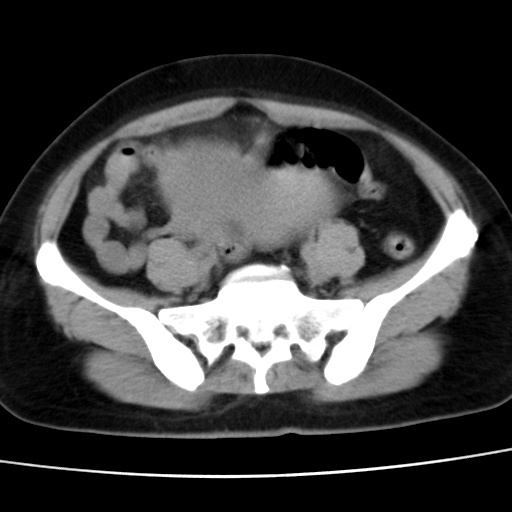

考虑多发子宫肌瘤,子宫直肠窝双囊性占位,另直肠周围脂肪密度增高,不知有何病史

患者因发烧来就诊,查彩超说是子宫颈旁边有无回声区,故来做ct。

子宫肌瘤,宫体部后方见液性密度影,是肠道还是子宫与直肠陷窝积液不好说,我觉得它的位置有点高

患者发热,而子宫直肠窝液性灶有明显边缘且局限且囊性,不除外为包裹性积液或脓肿

1)考虑子宫肌瘤可能性大。2)子宫后方囊性占位性病变,不排除卵巢囊肿可能。

考虑多发子宫肌瘤。子宫后方囊性占位性病变,不排除卵巢囊肿可能。